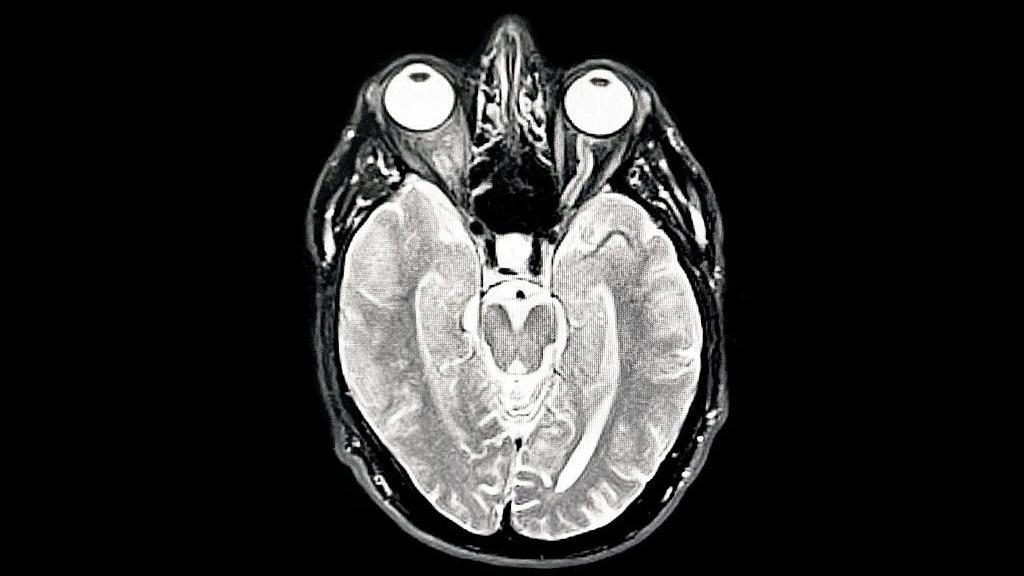

Una tomografía MIR del cerebro del fotógrafo muestra demencia temprana/Alzheimer

Getty Images